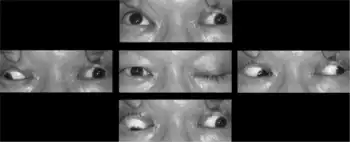

Signs and symptoms

A complete oculomotor nerve palsy will result in a characteristic displacement outward (exotropia) and downward (hypotropia). The outward displacement occurs because the lateral rectus muscle (innervated by the sixth cranial nerve) maintains muscle tone in comparison to the paralyzed medial rectus. The downward displacement occurs because the superior oblique muscle (innervated by the fourth cranial or trochlear nerve) is unantagonized by the paralyzed superior rectus, inferior rectus and inferior oblique. The affected individual will also have a ptosis, or drooping of the eyelid, and mydriasis (pupil dilation).